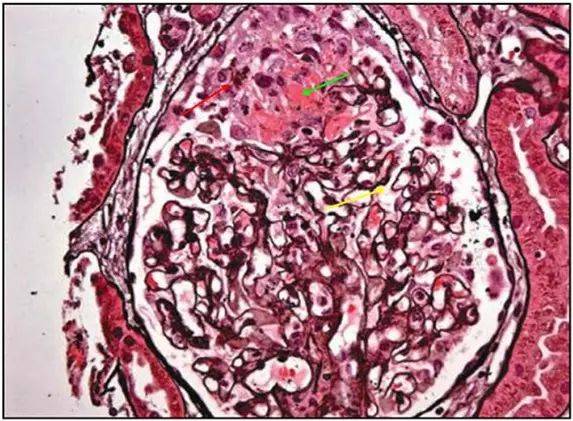

31 六胺银染色:红色箭头:肾小球基底膜上大量钉突形成

图 3 为pasm 染色:膜性肾病 ii 期,红色箭头:已经出现「钉突」,其实

a:肾小球毛细血管袢开放僵硬状,上皮侧钉突形成(pasm-masson